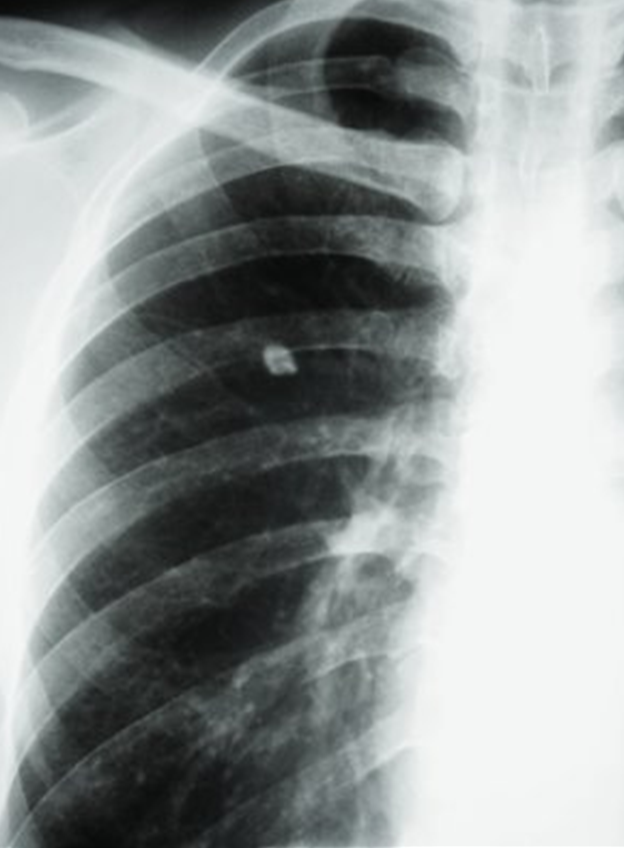

Same 55 y/o Vietnamese who has lived in US for 30 years, but he has the following CXR.

How do you manage him?

TreatÂ

high risk of progressing to TB diseaseÂ

TB Disease Case Rate By CXR Classification In Alaskan Natives

RUL some trouble

Infiltrate

Increase risk of disease progressionÂ

No increased risk of disease progression

Cavity in LUL

Even if culture negative is concerning

still concerning